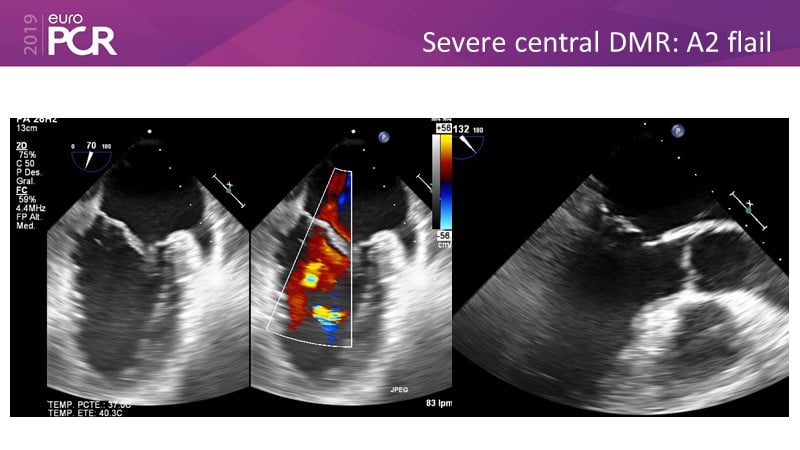

- To learn how will product innovation (Mitraclip NTR / XTR) drive improvement in procedural and clinical outcomes (EXPAND)